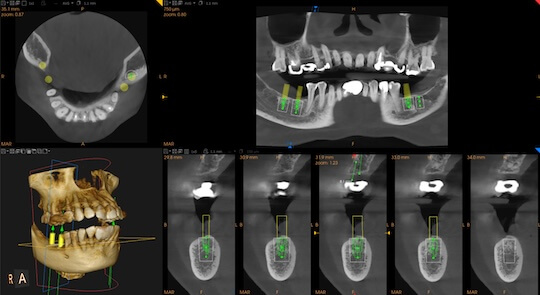

數碼化精準醫療,提升安全性

360 度全方位掌握神經位置、血管及牙骨密度,將手術風險降至最低。

進行精確影像拍攝,獲取牙床骨3D影像數據。

根據掃描結果,設計最理想的植體位置與角度。

引進頂尖 3D CBCT 與數碼化診斷系統。